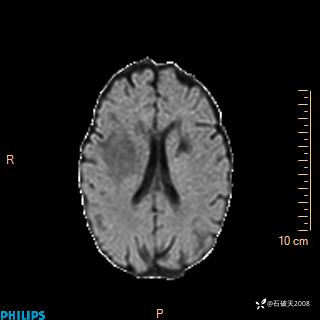

2020.11.14MR

FLAIR